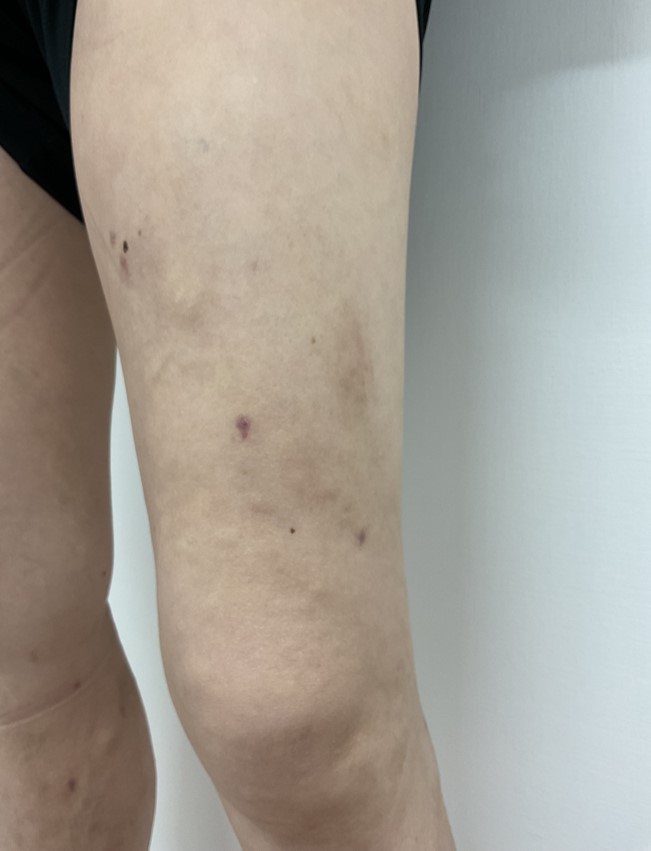

術前

術後